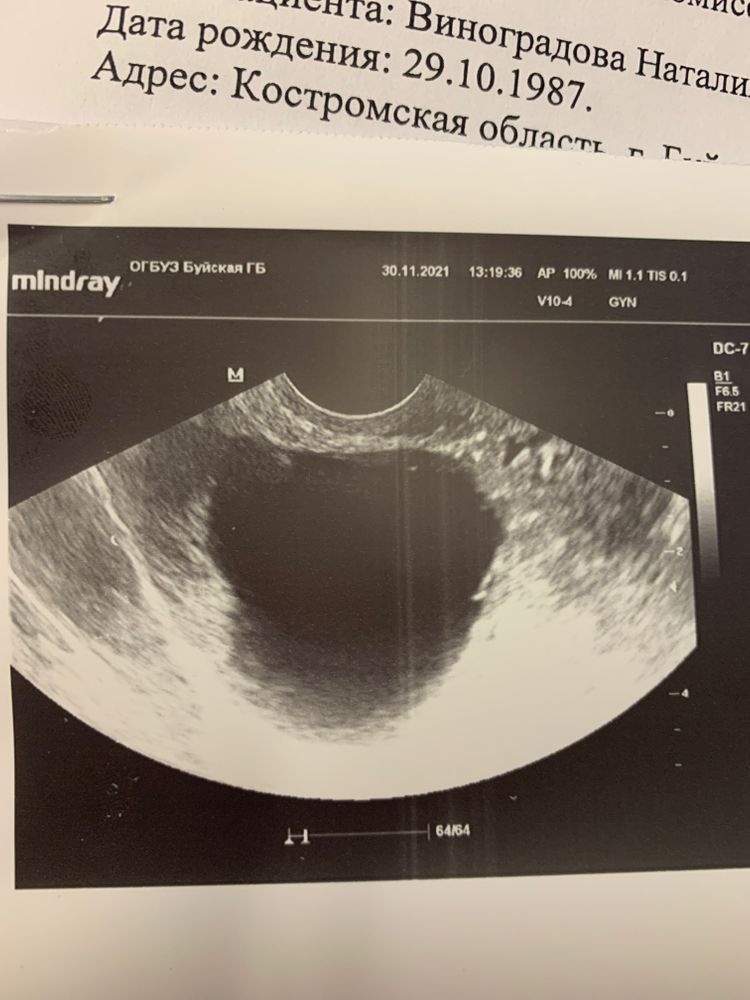

Девочки ходила на узи 5недель и 3 дня . Сказали что пусто , но поставили маленькую кисту на правом яичнике. Но делала тесты 1. Неделю назад 2. Сделан в ту пятницу. Дальше я поехала вам заключение . Подскажите может ли узист ошибиться или все таки тесты

Киста не выделяет хгч,а тесты реагируют только на хгч,судя по тестам хгч ещё мало,на УЗИ видно при хгч минимум 1 тысяча,в динамике хгч сдайте,как давно вам тест показал полоску? Может овуляция поздняя?

Пя видно обычно от 1000 хгч. Но очень зависит от качества аппарата. Сдавайте хгч и через недельку идите на УЗИ)

Тесты могут показать полоску при кисте. У меня в 5,5 аккушерских и 3 эмбриональных показало плодное яйцо 9 мм.